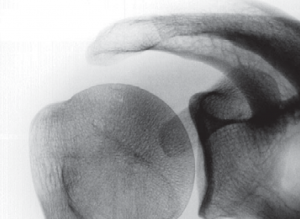

Unter dem Begriff Impingement-Syndrom versteht man die Zusammenfassung unterschiedlicher Ursachen, welche das Gleiten der Supraspinatussehne unter dem Schulterdach behindern. Ursache der Gleitbehinderung ist z.B. eine Formveränderung des Schulterdaches, die angeboren oder erworben sein kann. Auch Knochenausziehungen am Schultereckgelenk (Acromioclaviculargelenk, kurz: AC-Gelenk) als Ausdruck einer Schultereckgelenks-Arthrose können zu einer Einengung des subacromialen Raumes und somit zur Gleitbehinderung der Supraspinatussehne führen. Das ständige Reiben der Sehne gegen den Knochen bewirkt eine Schädigung (sog. Tendinopathie), die bis zum vollständigen Reißen der Sehne führen kann (Abb. 19, 20).

Die sog. Kalkschulter wird definiert als Kalkeinlagerung (Carbonatappatit) in die Sehnen der Rotatorenmanschette (Abb. 23), die durch unterschiedliche Faktoren ausgelöst sein kann. Am häufigsten ist davon die Supraspinatussehne betroffen. Die Erkrankung tritt häufig im 4. und 5. Lebensjahrzehnt auf und betrifft vorwiegend Frauen. Typischerweise finden sich wechselnde Phasen vollkommener Schmerzfreiheit und hochakuter Schmerzhaftigkeit.